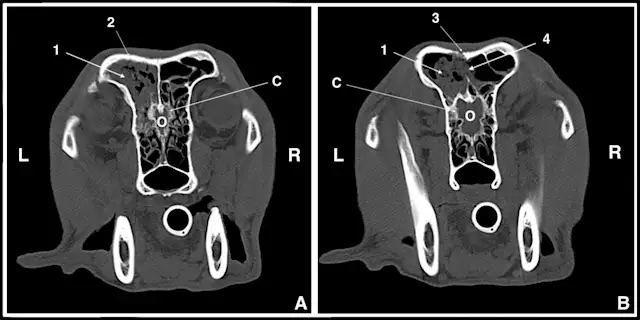

In this patient, CT (Video 1) revealed changes consistent with fungal rhinitis, including destruction of nasal turbinates and lesser flat bone destruction without evidence of a soft tissue mass (Figure 1) and irregular noncontrast-enhanced material in the frontal sinus, along with hyperostosis of the frontal bone (Figure 2).

Figure 1.

Two CT slices at different levels through the nasal cavity showing cavitated lesions secondary to turbinate destruction (D) in the left nasal cavity. There are milder changes in the right nasal cavity. (L = left, R = right)

For comparison, Video 2 shows CT of a dog with chronic rhinitis. Some patchy soft tissue/fluid density can be seen in the region of the nasal turbinates. However, no significant bony destruction is evident, nor is there any opacity within the frontal sinuses or frontal bone sclerosis.